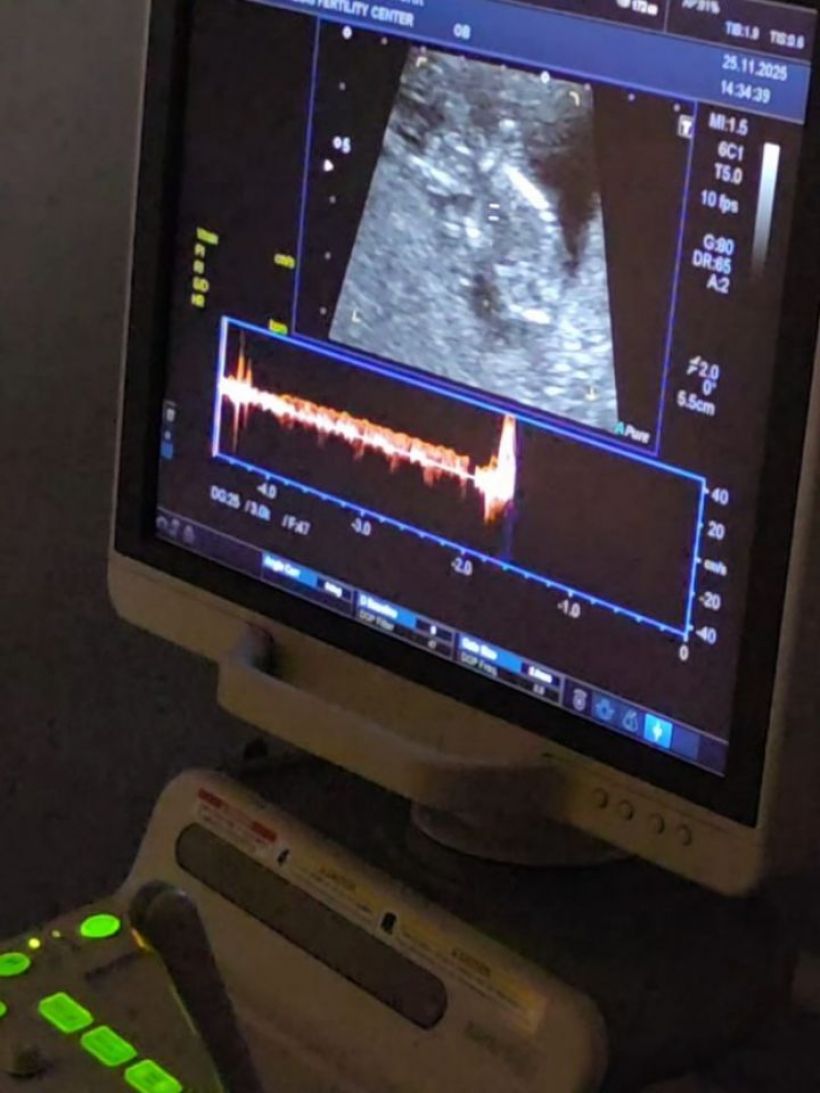

จนกระทั่งล่าสุดวันนี้ (28 พ.ย.) ลีซอ โพสต์ IG @leesawls14 เผยภาพอัลตร้าซาวด์เบบี๋ พร้อมเผยว่า "Finally วันนี้ก็มาถึง!!

คนที่มีบุตรยากอย่างเรา2คน วันนี้เราอยากจะบอกข่าวดีเบื้องต้นกับหลายๆคนที่ลุ้นและตื่นเต้นไปพร้อมกับพวกเราในการมีเบบี๋ตัวน้อย วันนี้เรามีเจ้าตัวน้อยนักสู้แบบผมมาแล้ว เย้ๆ ตอนนี้เฟียตตั้งครรภ์ได้12สัปดาห์แล้วครับ เป็นการใส่ตัวอ่อนครั้งแรกก็ติดเลย เก่งมากทั้งแม่และลูกแดดดี๊เลย แต่กว่าจะใส่ตัวอ่อนได้ เราเก็บไข่กันมาถึง5รอบ กว่าจะมีตัวอ่อนทองคํา เพียงหนึ่งเดียว เราต้องผ่านการอดทนและปัจจัยอีกหลายอย่างมาก" ท่ามกลางคนบันเทิงและแฟนคลับร่วมแสดงความยินดีล้นหลาม